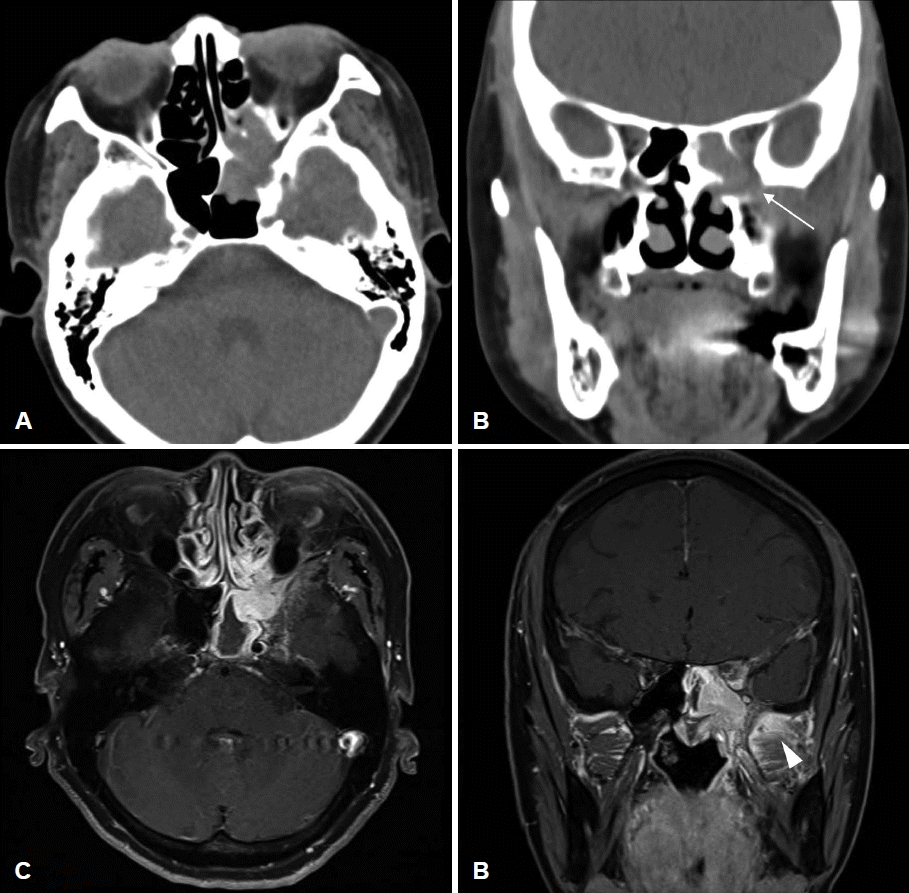

68세 여자 환자가 내원 3개월 전부터 시작된 좌측 안면부 통증 및 개구장애, 입술 감각 저하를 주소로 본원 신경과에 내원하였으며, 자기공명촬영에서 접형동의 종물 소견이 보여 이비인후과로 의뢰되었다. 과거력에서 고혈압, 고지혈증, 2형 당뇨, 불면증으로 경구 약제를 복용 중인 것 외에는 특이소견은 없었으며, 발열, 야간 발한은 호소하지 않았으나 최근 5개월간 63 kg에서 57 kg으로 6 kg의 체중 감소를 호소하였다. 비내시경검사에서 특이소견은 관찰되지 않았으며, 안과에서 시행한 시력검사, 시야검사, 안구운동검사에서 특이소견은 관찰되지 않았다. 부비동 컴퓨터 전산화단층촬영에서 좌측 접형동 및 후사골동의 연조직 음영이 관찰되었고 접형동 전외측벽의 골미란 및 골결손 소견이 보였다. 자기공명영상에서는 좌측 접형동 내에 T1, T2 강조영상에서 저신호를 보이고 gadolinium으로 균질하게 조영증가 되는 종양이 관찰되었다(Fig. 1).

A: Preoperative axial CT scan of the paranasal sinus shows soft tissue density opacity in the left sphenoid sinus and posterior ethmoid sinus. B: Coronal view shows bony erosion (arrow) of the anterolateral wall of the sphenoid sinus. C: Preoperative gadoliniumenhanced axial MRI shows a well-enhancing homogenous mass in the left sphenoid sinus. D: Coronal view shows increased enhancement at left masticator space (arrowhead), indicating tumor infiltration.